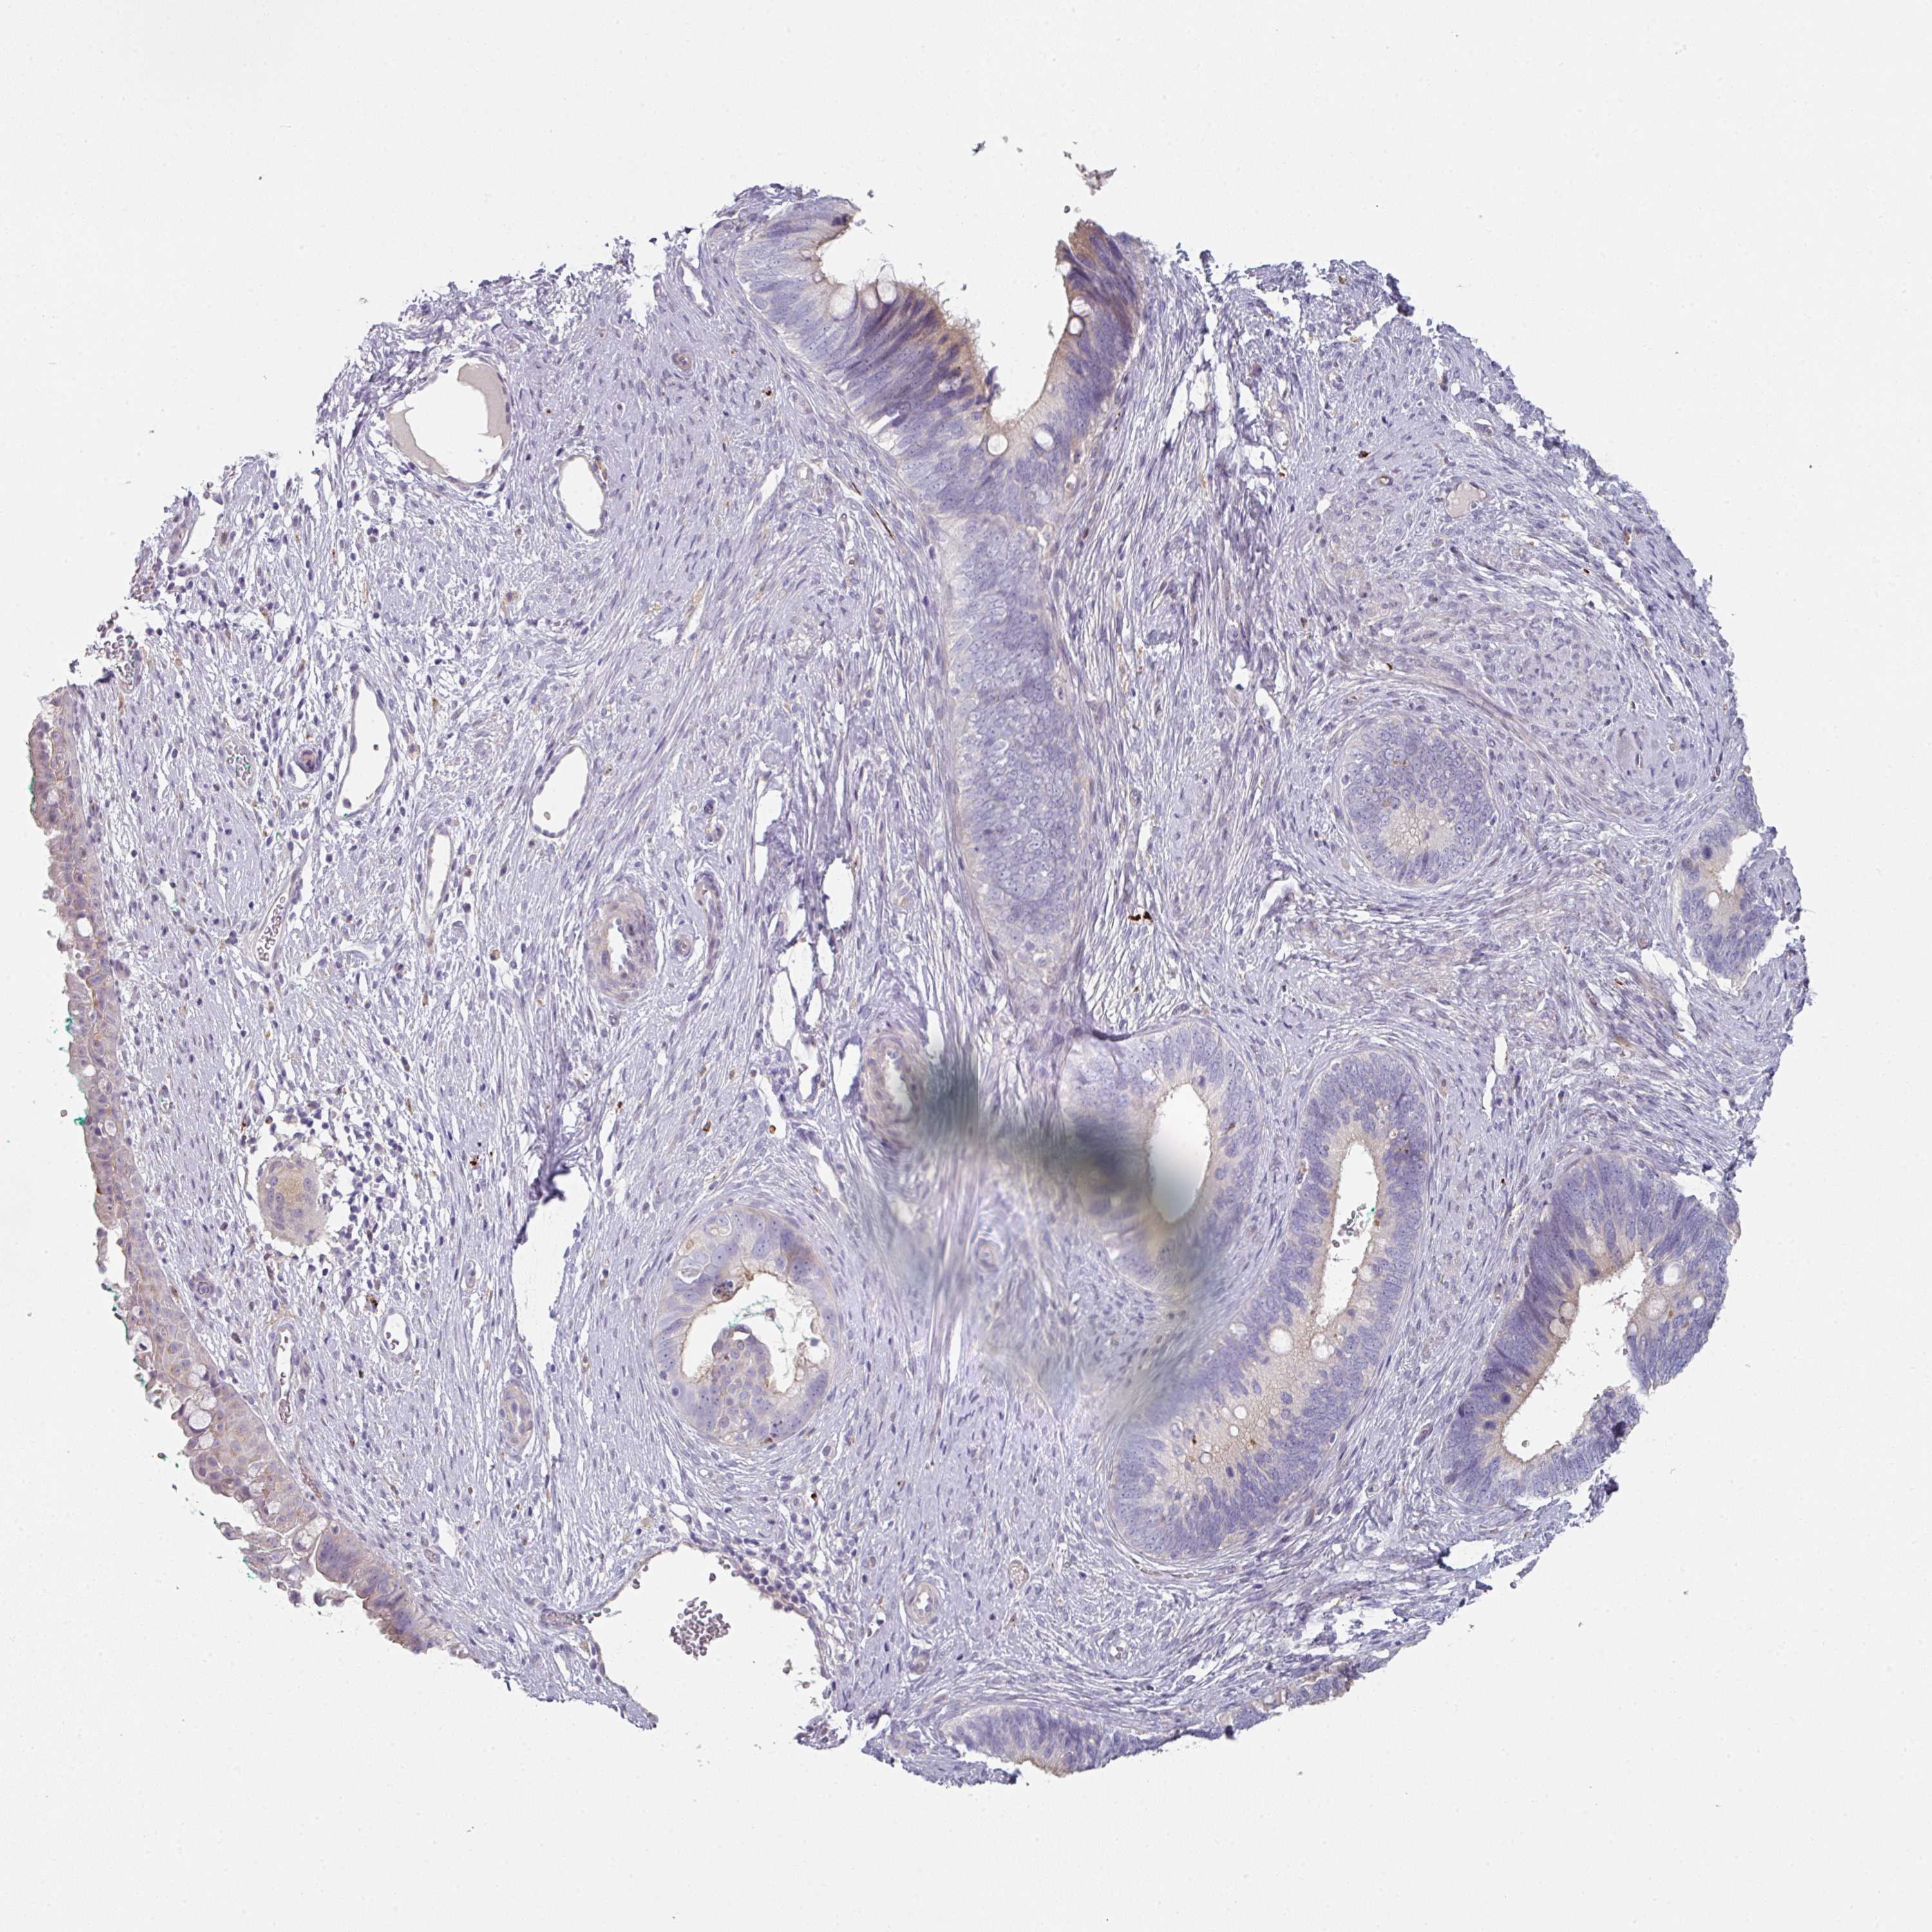

CERVICAL CANCER - Protein expressioni

A mouse-over function shows sample information and annotation data. Click on an image to view it in a full screen mode. Samples can be filtered based on level of antibody staining by selecting one or several of the following categories: high, medium, low and not detected. The assay and annotation is described here.

Note that samples used for immunohistochemistry by the Human Protein Atlas do not correspond to samples in the TCGA dataset.

Antibody stainingi

Antibody staining in the annotated cell types in the current human tissue is reported as not detected, low, medium, or high, based on conventional immunohistochemistry profiling in selected tissues. This score is based on the combination of the staining intensity and fraction of stained cells.

Each image is clickable and will lead to virtual microscopy that enables deeper exploration of all samples and also displays staining intensity scores, fraction scores and subcellular localization as well as patient and tissue information for each sample.

Antibody HPA052606

Antibody HPA077139

Staining

High

Medium

Low

Not detected

Intensity

Strong

Moderate

Weak

Negative

Quantity

>75%

75%-25%

<25%

None

Location

Nuclear

Cytoplasmic/membranous

Cytoplasmic/membranous,nuclear

Squamous cell carcinoma, NOS

Adenocarcinoma, NOS